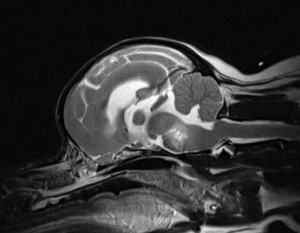

來到貝爾時,可憐的狗狗完全站不起來,並且呈現”頭部迴旋”的姿勢。在神經學檢查中也發現右眼斜視、雙眼不對稱垂直眼球震顫,威嚇試驗陰性等異常。神經科醫師馬上意識到這可能是在大腦至腦幹區域多病灶性的病變,因此馬上幫狗狗安排磁振造影掃描。

磁振造影下發現了在大腦、中腦及腦幹影像上可見多處瀰漫性高訊號改變。這正是造成狗狗生病的元凶!醫師也採取了腦脊髓液,發現了細胞數增多,並且在後續的培養中也沒有細菌或真菌的出現。

這正是不明原因腦膜腦脊髓炎 (MUO)典型的病例